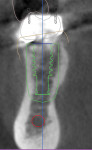

A CBCT image (Figure 2) and digital impression (Figure 3) were obtained for diagnosis and treatment planning. To facilitate this, the CBCT image and impression were merged into the implant planning software for evaluation. Tooth No. 30 was removed from the virtual model, and a virtual restoration was created (Figure 4). Next, the vital structures and osseous anatomy were identified, and a virtual implant was planned (Figure 5 and Figure 6). A virtual fully guided surgical template was created (Figure 7) and then sent to the in-office printer for guide fabrication (Figure 8 and Figure 9). Using a flapless technique, the crown of tooth No. 30 was removed, and the necrotic roots were sectioned and surgically removed (Figure 10 and Figure 11). Following this, the CT template was placed, the osteotomies were completed, and the implant was placed in a guided fashion with 60 Ncm of torque (Figure 12 and Figure 13). After the osseous socket was grafted with allogenic bone, a healing abutment was placed, and the tissue was stabilized without mobilization using 3-0 chromic sutures (Figure 14 and Figure 15). An immediate post-operative CBCT scan was used to verify that the implant was placed as planned (Figure 16 and Figure 17).